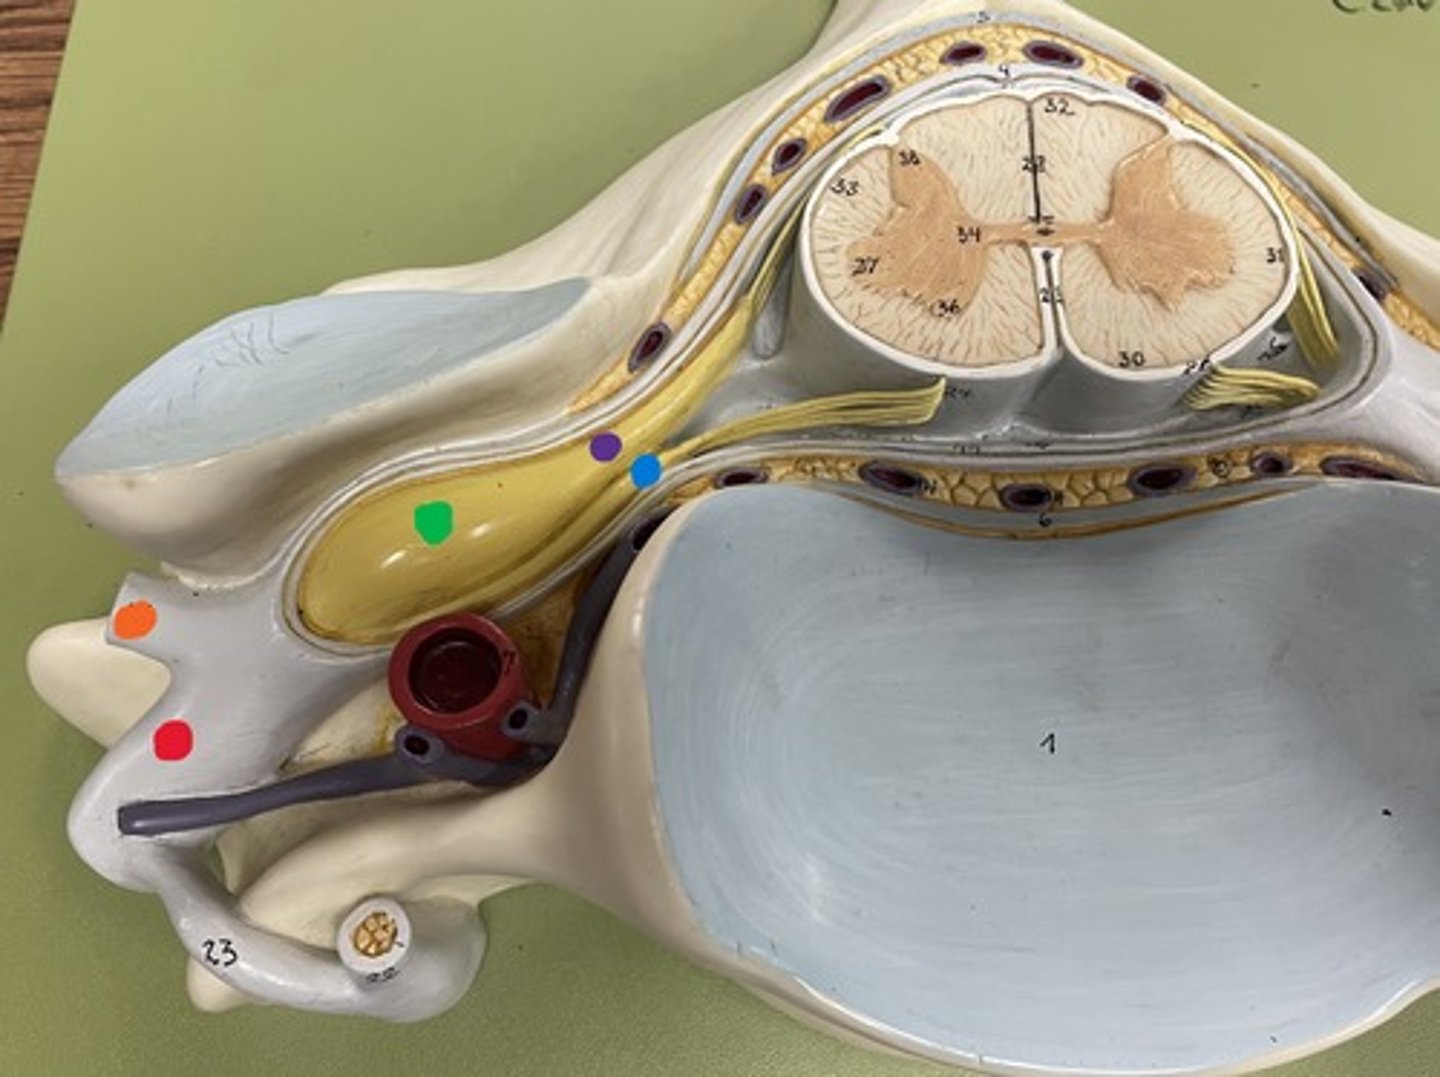

Cervical enlargement

Blue

Lumbar enlargement

Purple

Conus medullaris

Green

Cauda equina

Red

Filum terminale

blue

Epidural space

purple

Subdural space

between red and blue

Subarachnoid space

between red and green

Posterior root

purple

Posterior root ganglion

green

Posterior ramus

orange

Anterior root

blue

Anterior ramus

red